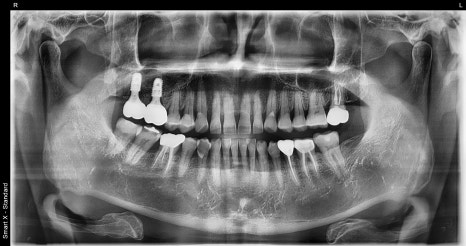

A detailed examination was carried out through panoramic imaging and CT scans.

The examination results showed not a simple cavity or crown fracture, but cracks extending to the root area.

Also, because upper molars are close to the maxillary sinus, bone grafting or sinus lifting is often needed if the bone is thin or inflammation is severe.

Position of the maxillary sinus

The bone height in the upper molar area was insufficient, so a small-scale sinus lift was needed.

At the follow-up visit, panoramic imaging confirmed that the implant was settling in well.